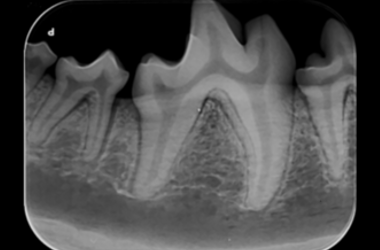

Formation en radiologie dentaire vétérinaire

Suivez notre formation en radiologie dentaire vétérinaire et testez nos appareils. Prochaine date de formation: Mardi 15 octobre 2019 Düdingen Mardi 19 novembre 2019 Aarau Mardi 3 décembre 2019 Lausanne Plus d‘informations: Formations radiologie dentale